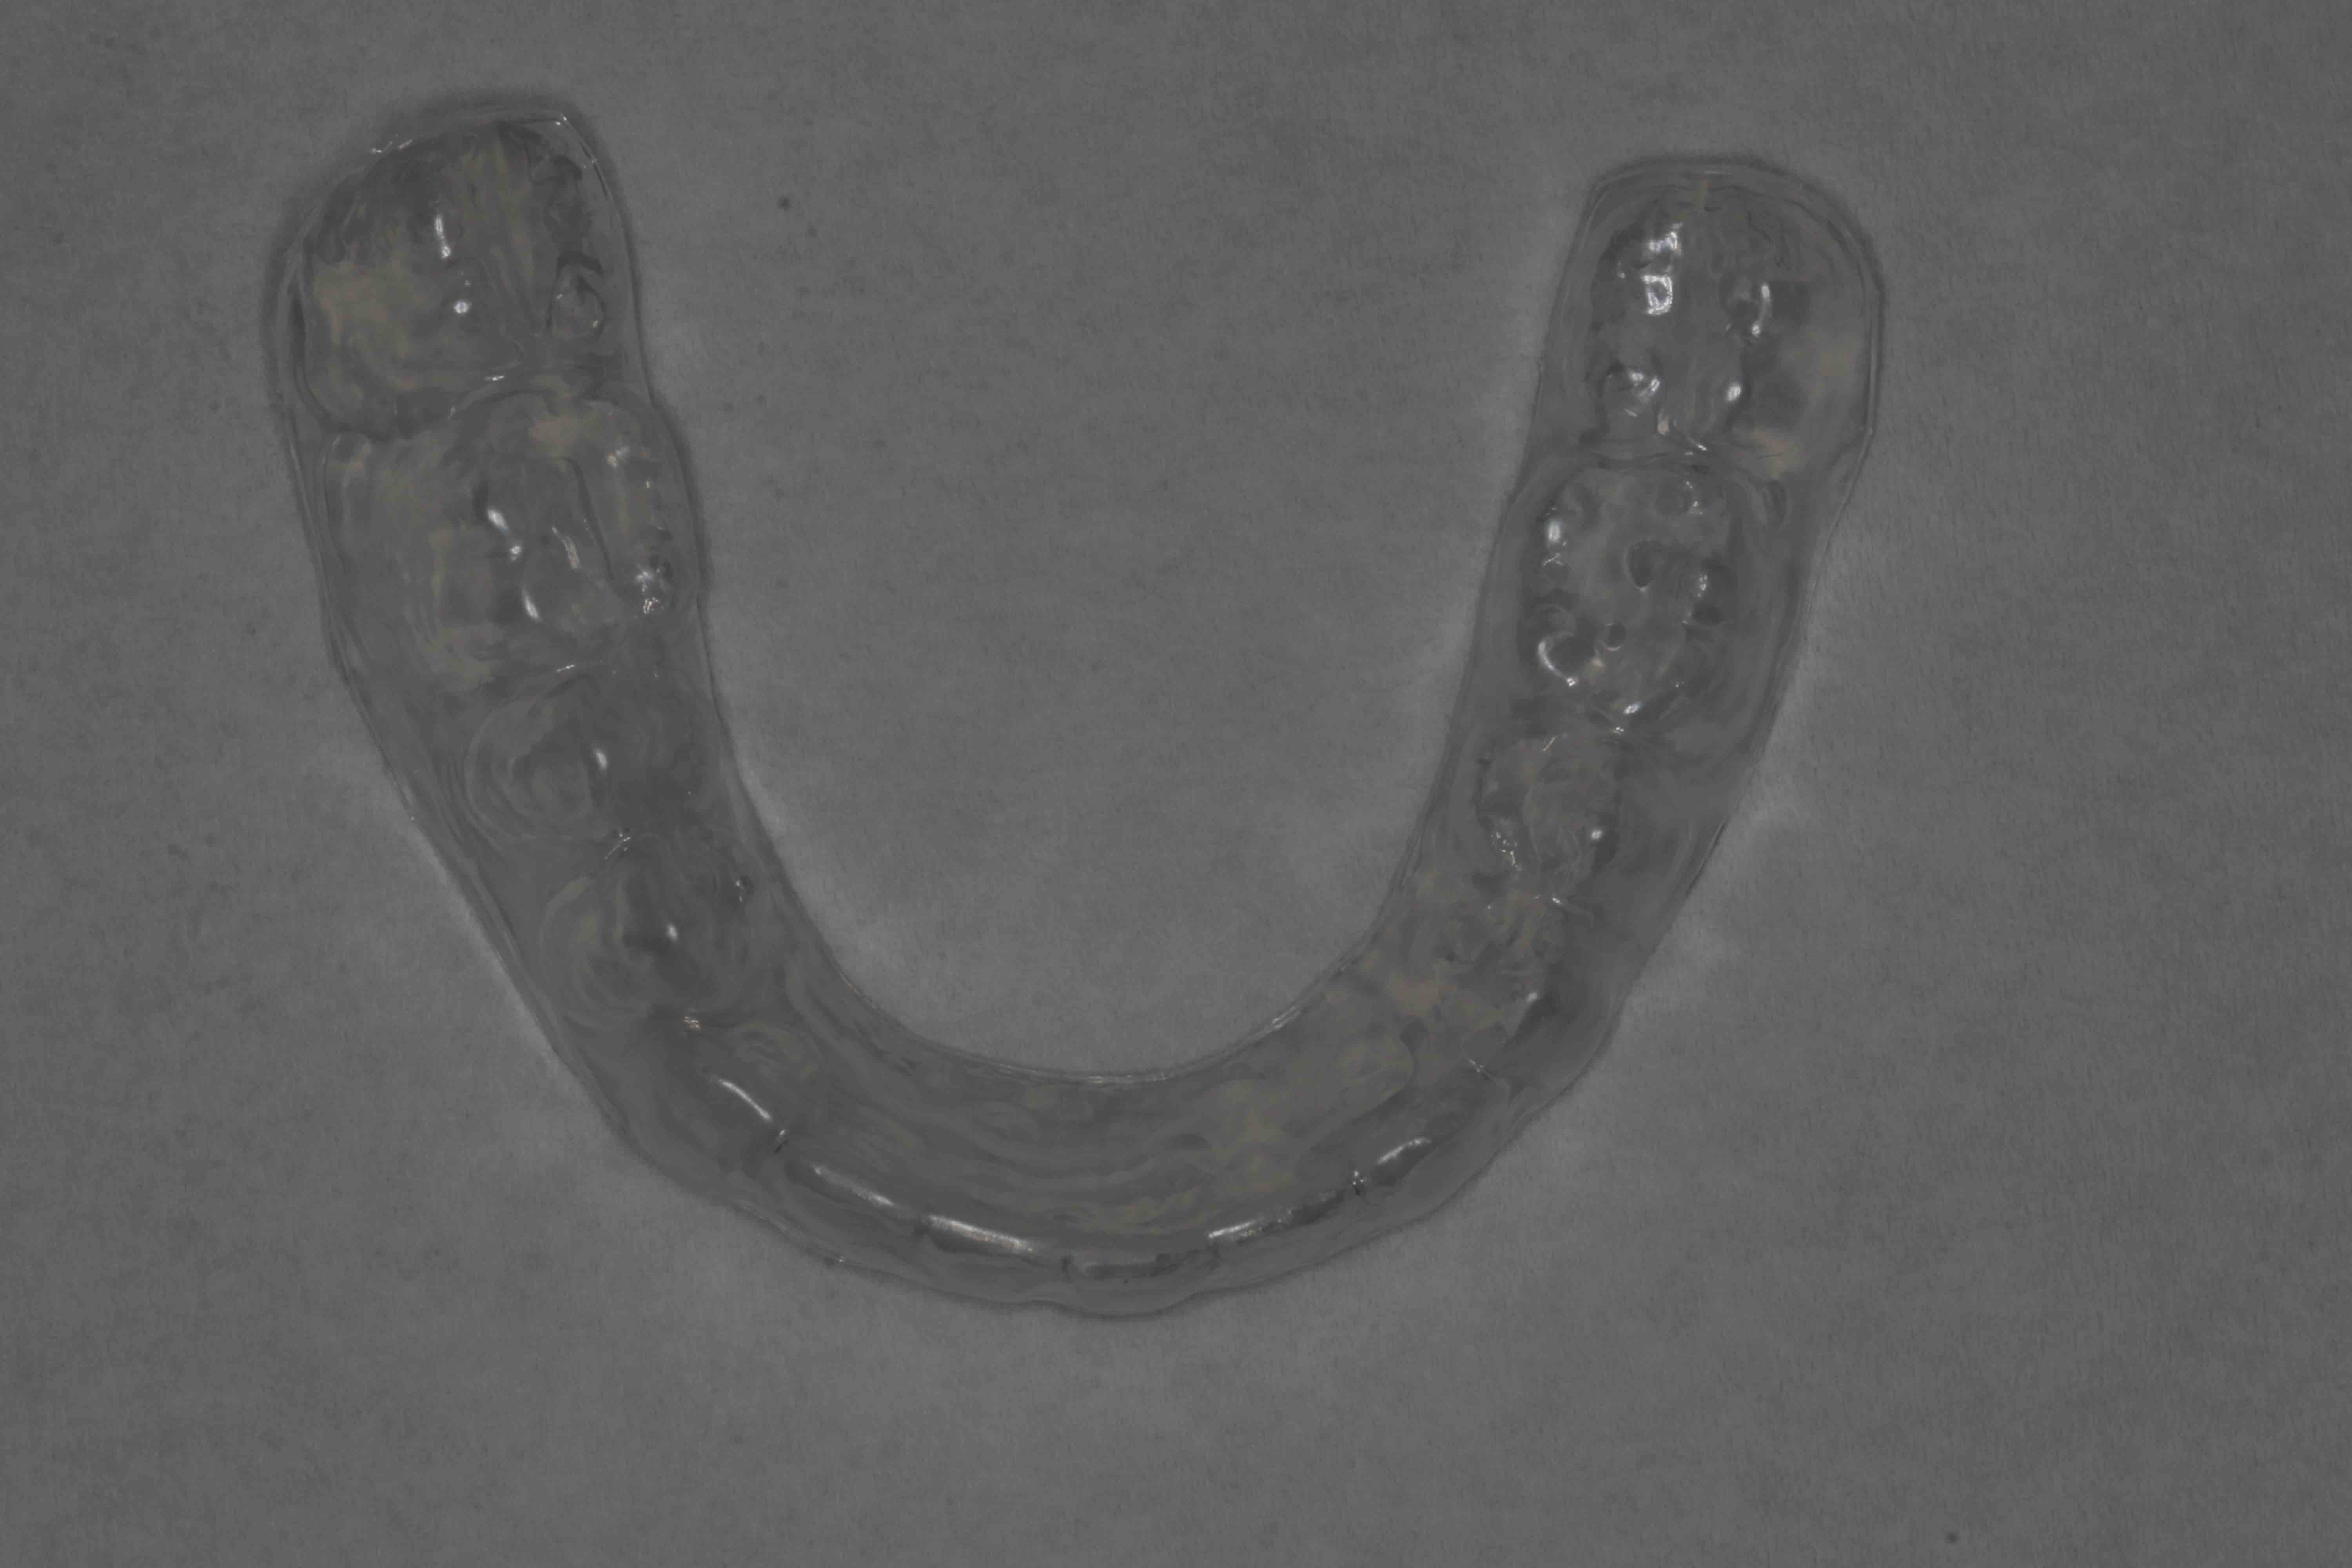

Etter avsluttet aktiv behandling med streng legges det vekt på å bevare resultatet. Pasienten får retensjonsutstyr etter instruksjon, med plater og strenger i både over- og underkjeven. Videre oppfølging avtales for å sikre stabil tannstilling. Pasient og foresatte innkalles til gjennomgang av behandlingen.